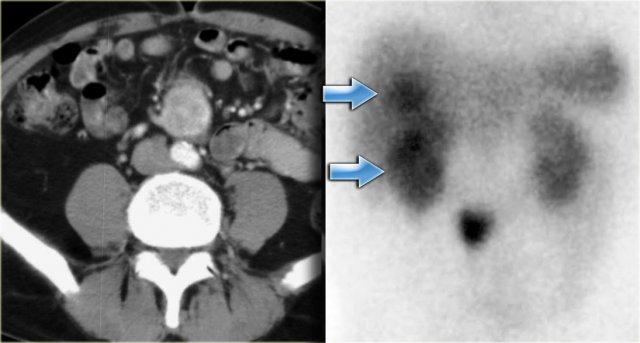

Hình bên trái là một bệnh nhân khác mắc u carcinoid.

Hình bên phải là octreoscan, dương tính trong 85% các trường hợp u carcinoid, do đó đây có thể là công cụ hỗ trợ rất hữu ích trong chẩn đoán phân biệt.

Trong trường hợp này, chúng ta cũng có thể phát hiện di căn gan trên hình chụp (mũi tên xanh dương).

Lưu ý không có hoạt động của khối u nguyên phát ở ruột non.

Điều này thường gặp vì khối u nguyên phát có thể khá nhỏ.